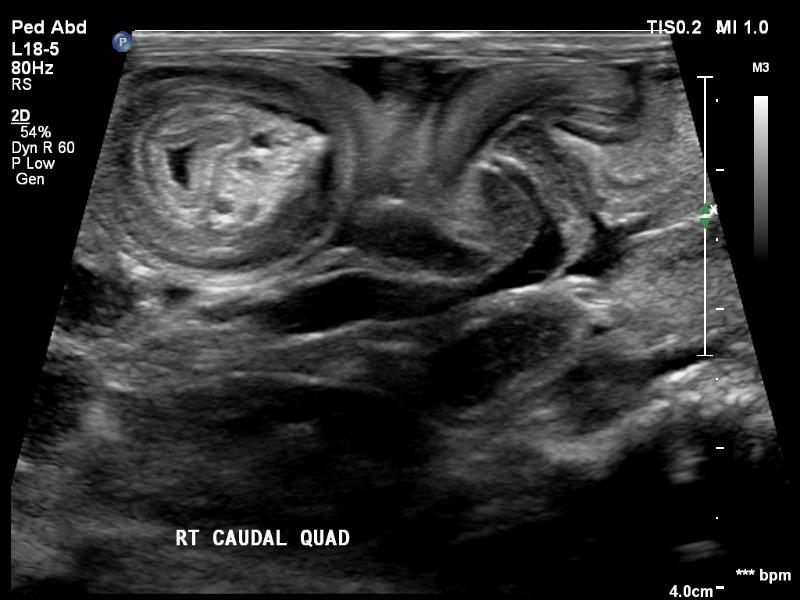

- Kidneys and Urinary Bladder